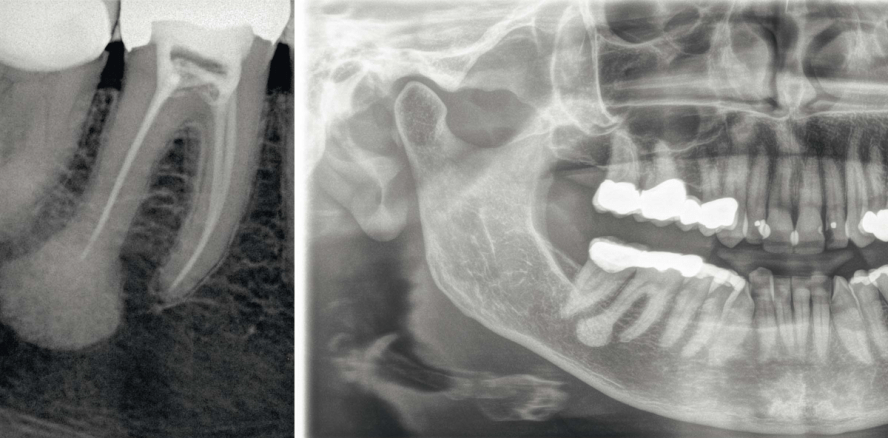

Auf dem OPT stellte sich an der distalen Wurzel des Zahnes 46 eine halbmondförmige ca. 10 mm große röntgendichte Verschattung dar und eine ca. 3 mm große eiförmige Verschattung dorsal davon in Verbindung mit einer kleinen Auftreibung besagter Wurzelspitze. Die Vitalitätsprüfung des Zahnes 46 war eindeutig positiv. Die Verdachtsdiagnose lautete „sklerosierende Ostitis 46“.

Bei einer erneuten röntgenologischen Untersuchung am 17. August 2015 hatte sich die Verschattung deutlich vergrößert und in der Form verändert. Es imponierte nunmehr eine birnenförmige gleichmäßig strukturierte feinkörnig dichte Raumforderung in Verbindung mit einer starken Auftreibung der Wurzelspitze und kaudal davon eine halbmondförmige gleichartige Struktur, getrennt durch einen sehr feinen Spalt. Der Zahn 46 reagierte immer noch eindeutig vital auf Kältetest. Palpatorisch war im Bereich der distalen Wurzel des 46 vestibulär eine harte und nicht druckdolente Auftreibung zu tasten. Alle Anzeichen einer akuten Entzündung fehlten, auch die regionalen submandibulären Lymphknoten waren unauffällig. Eine digitale Volumentomografie lehnte die Patientin aus Kostengründen ab.